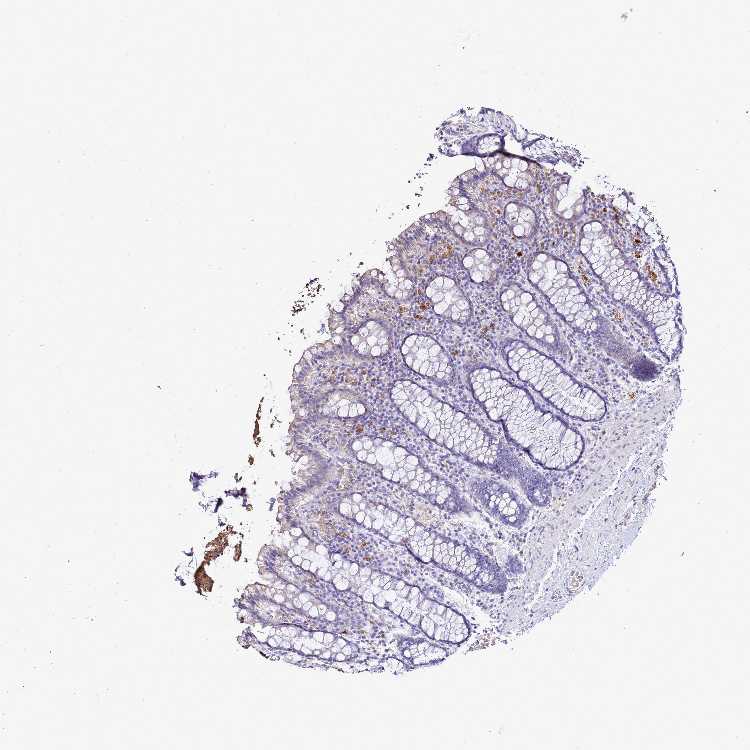

S100A2